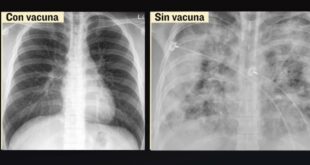

· La doctora Célida Duque Molina, directora de Prestaciones Médicas, subrayó que la vacuna es eficaz y segura. · Comentó que los Módulos de Atención Respiratoria del Seguro Social han contribuido a detener los contagios. MÉRIDA, Yuc., 26 de julio 2021.- Ante el cambio de semáforo epidemiológico en varios estados …